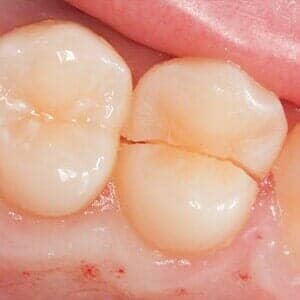

Some people are quite aggressive in clenching their teeth while they sleep and others actually grind them and wear them down. These activities are often associated with jaw joint pain (TMJ) and headaches or migraines. It can also lead to cracked or broken teeth as well as your teeth becoming loose or cold sensitivity. Most commonly this is treated with a variety of mouth guards or bite adjustments. In some cases, injections are done in the chewing muscles which is used to reduce pain and hyper-activity.